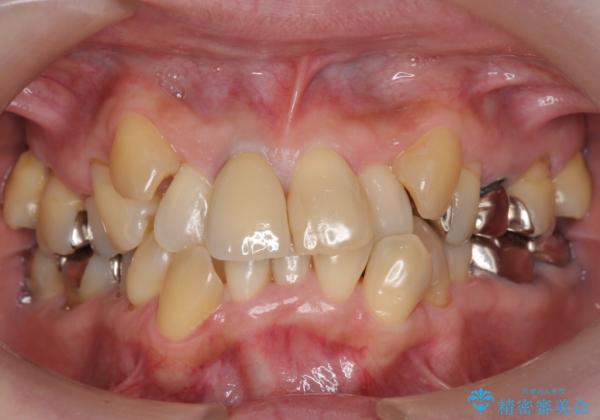

50代女性 八重歯を矯正治療 歯並びの中等度のがたつき

- 八重歯の矯正を希望されて来院。

歯は入りきらないため、通常の抜歯矯正を行いました。

歯がご年齢的に動きにくいため、被せ物のやり替えを含めて治療期間の短縮を図りました。

矯正治療自体は2年半、虫歯治療等で1年ほどかかっています。

詰め物や被せ物のやり替えも併せて行っているため、治療期間を比較的短縮できました。